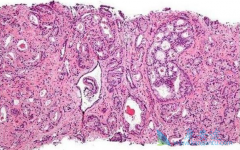

肾细胞癌是最常见的肾脏恶性肿瘤之一,因为有30%左右的肾细胞在初诊的时候已经被转移,随着对肿瘤生物学特性的深入了解,尤其是在血管内皮生长因子(VEGF)通路和哺乳动物雷帕霉素靶蛋白(mTOR)通路在肾细胞癌发生发展中的作用得到明确后,靶向药物开始进入 ...

据相关的数据统计, 前列腺癌 在我国的发病率呈现不断上升的趋势,年增长速度已经超过了5%,位居所有肿瘤增长率的前两位。根据前列腺癌的不同分期,患者的治疗方式和预后也有所不同。精准判断前列腺癌的分期,可以帮助专业的医生来确定癌肿的范围和活性 ...

对于前列腺癌患者,定期筛查肿瘤标志物可在疾病的早期发现存在的风险因素。若在体检的无症状人群中发现可疑者,通过风险因素评估,确定高危人群后,再及时展开进一步检查和治疗,可有效降低患者死亡率。血清前列腺特异性抗原(PSA)是前列腺癌重要且敏感 ...